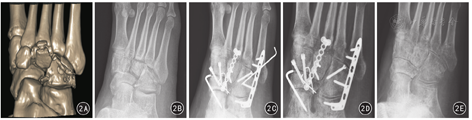

本组73例(73足)顺利完成手术,手术时间66~138 min,平均82 min。术中出血量30~80 mL,平均52 mL。患者术后切口均一期愈合,无伤口感染及切口皮肤坏死等并发症。78例患者均获随访,随访时间2~9年,平均33个月。5例(5足)保守治疗患者,伤后6~8周骨折畸形愈合。73例(73足)手术治疗患者中,9例(9足)切开复位螺丝钉辅助克氏针内固定,骨折复位不充分,术后6~8周畸形愈合。畸形愈合共14足,均出现足外侧柱短缩,中前足外展畸形、骨关节炎、中足外侧疼痛,均未行特殊干预。其余64例(64足)手术治疗患者采用微型钢板桥式支撑内固定,骨折复位充分,术后8~12周骨折及植骨愈合,患者随访期间无微型钢板引起的腓骨肌腱激惹、断裂,无骨关节炎、足外侧柱短缩及骰骨处明显疼痛等相关并发症发生。78例患者术后1年根据AOFAS标准评分75~97分,平均93.5分;依据评分评定足部功能:优64例(64足),良14例(14足);其中5例保守治疗患者足部功能均为良。典型病例图2。